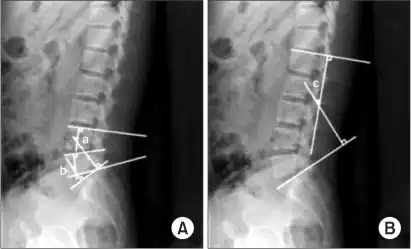

a,b)Cobb's angle for segmental lordosis and whole lumbar lordosis

X-ray of lumbar hyperlordosis

Measurement and diagnosis of lumbar hyperlordosis can be difficult. Obliteration of vertebral end-plate landmarks by interbody fusion may make the traditional measurement of segmental lumbar lordosis more difficult. Because the L4–L5 and L5–S1 levels are most commonly involved in fusion procedures, or arthrodesis, and contribute to normal lumbar lordosis, it is helpful to identify a reproducible and accurate means of measuring segmental lordosis at these levels.[16][17] A visible sign of hyperlordosis is an abnormally large arch of the lower back and the person appears to be puffing out his or her stomach and buttocks.

Precise diagnosis is done by looking at a complete medical history, physical examination and other tests of the patient. X-rays are used to measure the lumbar curvature. On a lateral X-ray, a normal range of the lordotic curvature of between 20° and 60° has been proposed by Stagnara et al., as measured from the inferior endplate of T12 to the inferior endplate of L5.[18] The Scoliosis Research Society has proposed a range of 40° and 60° as measured between the upper endplate of Th12 and the upper endplate of S1.[18] Individual studies, although using other reference points, have found normal ranges up to approximately 85°.[18] It is generally more pronounced in females.[18] It is relatively constant through adolescence and young adulthood, but decreases in the elderly.[18]